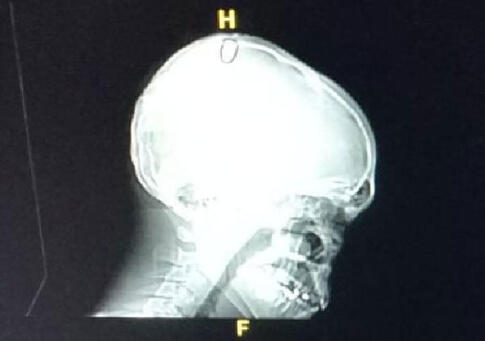

TOMOGRAFİDE MERMİ ÇEKİRDEĞİ GÖRÜLDÜ

Olay yerine gelen acil sağlık ekipleri, yaptıkları ilk müdahalede gencin yorgun mermiyle vurulmuş olabileceğini değerlendirerek R.A.'yı ambulans ile Kocaeli Devlet Hastanesi'ne kaldırdı. Gencin hastanede çekilen tomografisinde başındaki mermi çekirdeği görülürken, hayati tehlikesinin olmadığı öğrenildi. R.A., başındaki mermi çekirdeğinin çıkarılması için ameliyata alındı. Polis R.A.'ya isabet eden mermiyi ateşleyen kişiyi bulmak için çalışma başlattı.